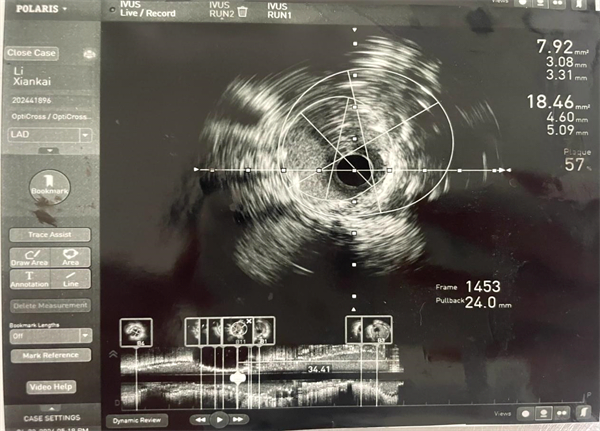

在充分评估患者病情后,心血管内科介入团队在科室副主任彭宇带领下进行IVUS检查,明确血管内斑块性质及管腔狭窄严重程度。IVUS结果提示:左主干开口至体部纤维斑块,最小管腔面积7.64mm,前降支近中段可见纤维钙化斑块,斑块负荷重,最小管腔面积 1.81mm。

PCI 术前IVUS图像